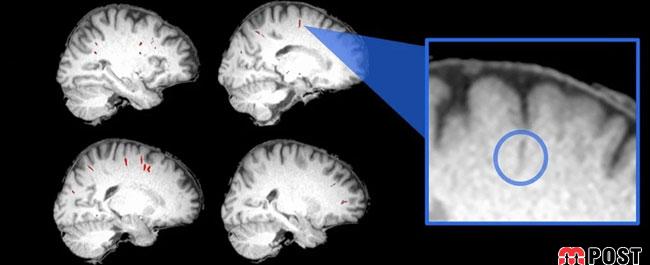

در این تحقیق دانشمندان مغز ۱۵ فضانورد را قبل و بعد از اقامت یلند مدت به ایستگاه فضایی بینالمللی اسکن کردند. محققان برای اندازهگیری فاصلۀ اطراف رگهای خونی مغز، از MRI استفاده کردند. دانشمندان چگونگی تغییرات این فاصله را قبل از سفر به فضا، بلافاصله پس از بازگشت از فضا و همچنین مدتی پس از بازگشت، بررسی کردند.